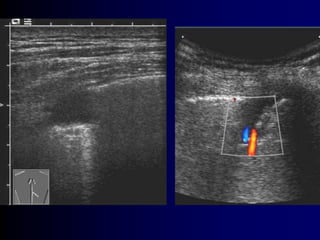

Alveolar-interstitial syndrome

Multiple B-lines - « comet-tails » - interstitial edema

(B1)

7 mm apart « B lines » thickened interlobular

septa

D Lichtenstein et al AJRCCM 156 : 1640-1646 , 1997JJR 25 05http://www.reapitie-

Coalescent B lines - « comet-tails » - alveolar

edema

3 mm apart « B lines » ground-glass

areas

Multiple B-lines -« comet-tails » - interstitial edema (B1) 7 mm apart « B lines » thickened interlobular septa D Lichtenstein et al AJRCCM 156 : 1640-1646 , 1997JJR 25 05http://www.reapitie- http://www.reapitie- 02 09 2012

D Lichtenstein etal AJRCCM 156 : 1640-1646 , 199730 11 2011 Coalescent B lines - « comet-tails » - alveolar edema 3 mm apart « B lines » ground-glass areas http://www.reapitie- 02 09 2012